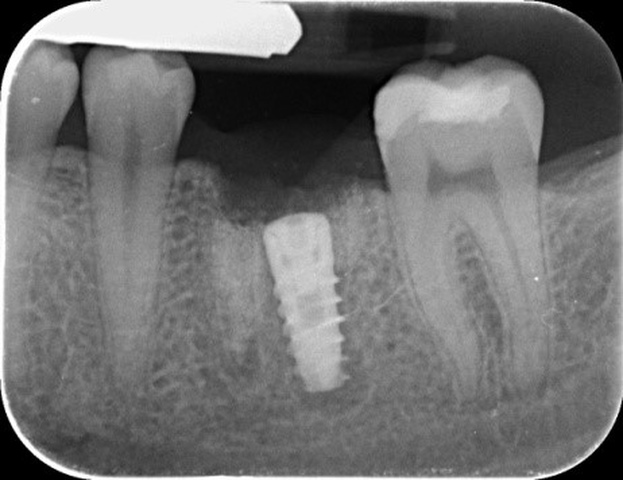

W znieczuleniu miejscowym przeprowadzono minimalnie inwazyjny zabieg usunięcia zęba metodą separacji korzeniowej. Następnie założono szablon implantologiczny i używając systemowej sekwencji wierteł, wypreparowano łoże pod wszczep, który następnie wprowadzono, uzyskując stabilizację pierwotną; zabezpieczono go śrubą zamykającą (Implant Seven, MIS). Wolne przestrzenie zębodołu poekstrakcyjnego wypełniono materiałem kościozastępczym (Bio-Oss, 0,25-1 mm, Geistlich Biomaterials, Szwajcaria), a całość pokryto błoną z osocza bogatopłytkowego oraz lateksowym koferdamem, utrzymywanymi szwami, które pozostawiono na 7 dni (ryc. 7-13).

Ryc. 9. Wprowadzony wszczep.

Ryc. 13. Kontrolne zdjęcie rentgenowskie – prawidłowo spozycjonowany wszczep.